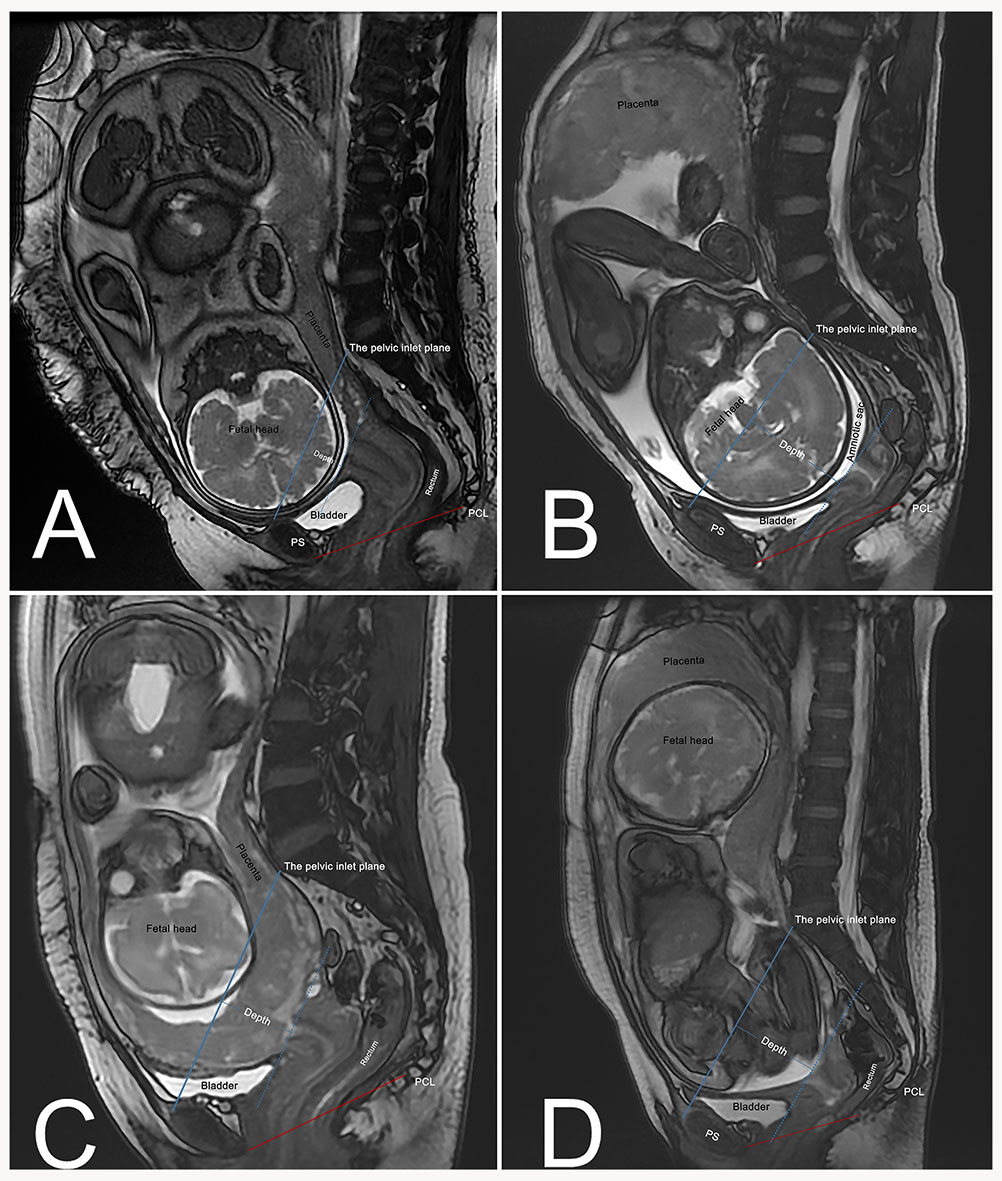

An additional line drawn from the pubic symphysis’ superior margins to the sacral promontory defines the pelvic inlet plane for pregnant women [20]. The depth of the fetus and its appendages in the pelvis was defined as the greatest distance from the pelvic inlet plane to the fetal presentation or the inferior part of the placenta or amniotic sac (Fig. 2). All measurements were performed in millimeters.

Fig. 2. Engagement depth of fetal/placental structures relative to pelvic inlet plane. (A) Cephalic presentation with shallow engagement (Depth = 22 mm). (B) Cephalic presentation with deep engagement (Depth = 65 mm; amniotic sac as the most inferior part entering the pelvis). (C) Placenta previa (Depth = 40 mm; placenta as the most inferior part entering the pelvis). (D) Breech presentation (Depth = 60 mm; amniotic sac as the most inferior part entering the pelvis). Blue solid line: Pelvic inlet plane, drawn from the superior margin of the pubic symphysis to the sacral promontory. Blue dashed line: Parallel to the pelvic inlet plane, passing through the lowest point of the fetus or its associated structures. Depth: Perpendicular distance between the two parallel lines, quantifying the extent of fetal/placental descent into the pelvis. Red solid line: Pubococcygeal line (PCL).